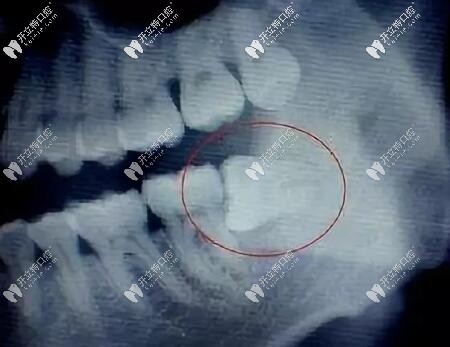

阻生智齒圖片

但有一些智齒,傾斜長的,或者水平長的,或者是埋在骨頭里的,有些還壓著神經(jīng)管的,這時(shí)候就需要將牙肉切開,去除周圍的骨頭。

智齒牙片

尤其橫生智齒,一顆橫生的智齒,普通的鉗子是拔不出來的,需要拿出渦輪機(jī)磨開,醫(yī)生還要判斷感染的風(fēng)險(xiǎn)等等,所以這些背后體現(xiàn)的是醫(yī)生的經(jīng)驗(yàn)。